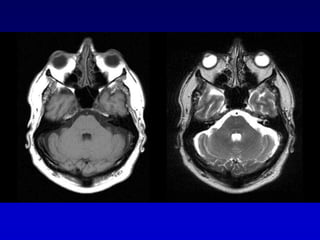

Glomus timpánico

Carótida aberrante

Bulbo yugular dehiscente